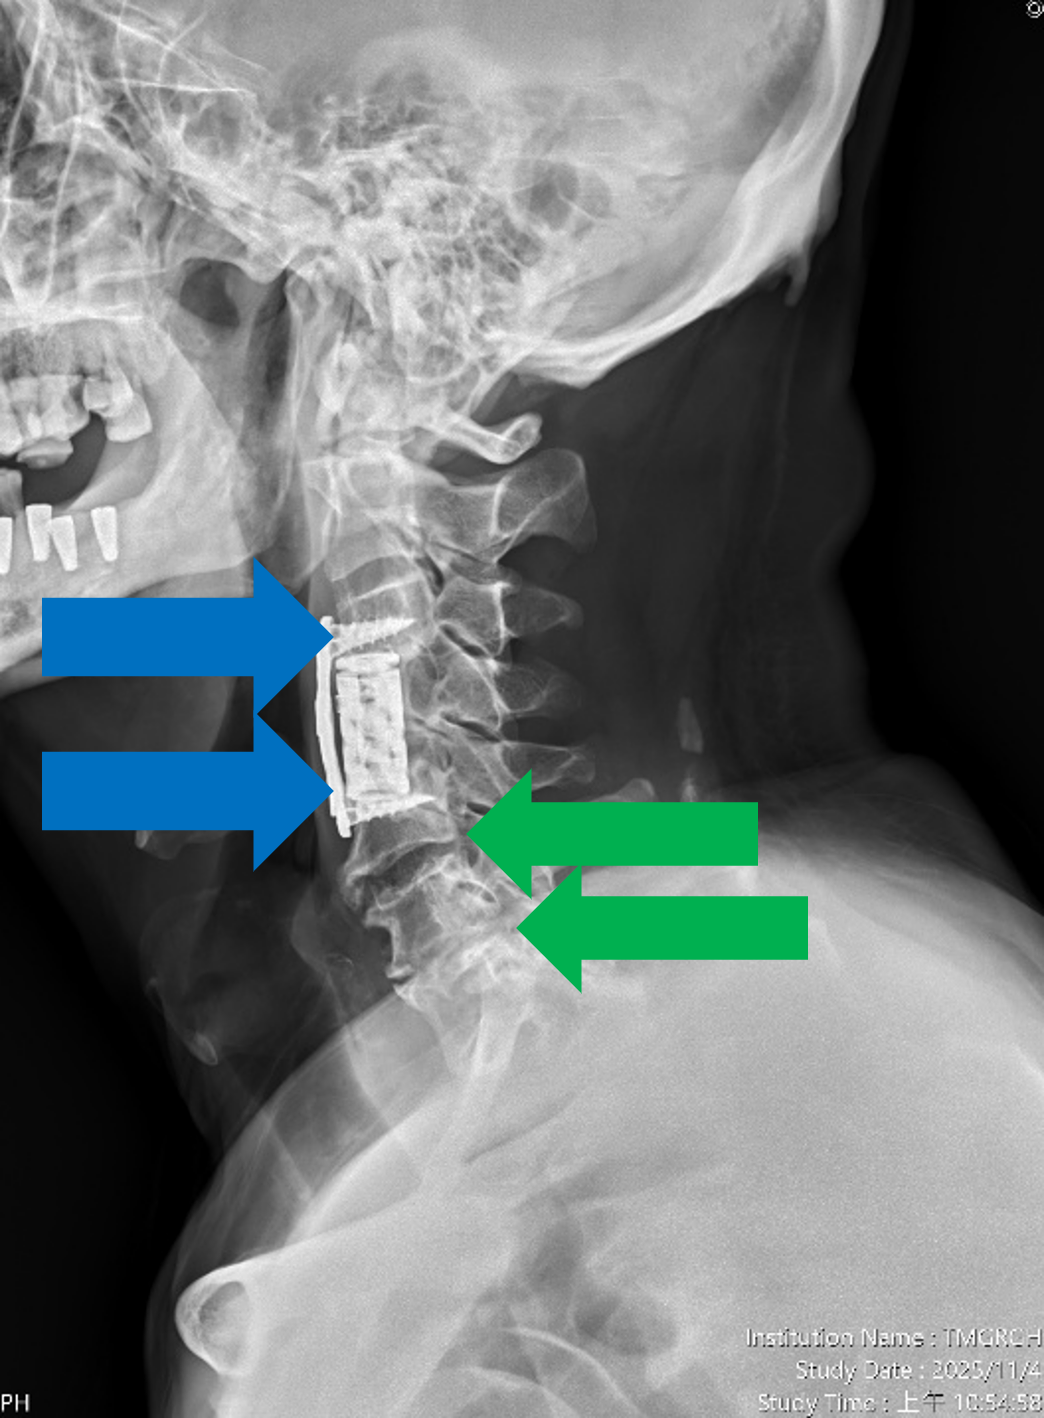

圖一、【治療前】患者曾於年初接受其他醫療院所執行第四頸椎體切除,籠狀支架融合(如左圖紅色箭頭)及第三第五頸椎骨釘骨板固定手術(如右圖藍色箭頭),並有第五第六及第六第七頸椎間盤退化及狹窄情況(如右圖綠色箭頭)。